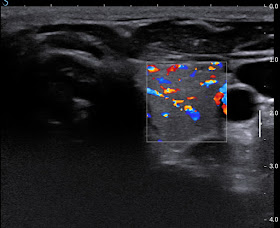

Ultrasound  reported   edema with  hypervascular  soft tissue of the foot